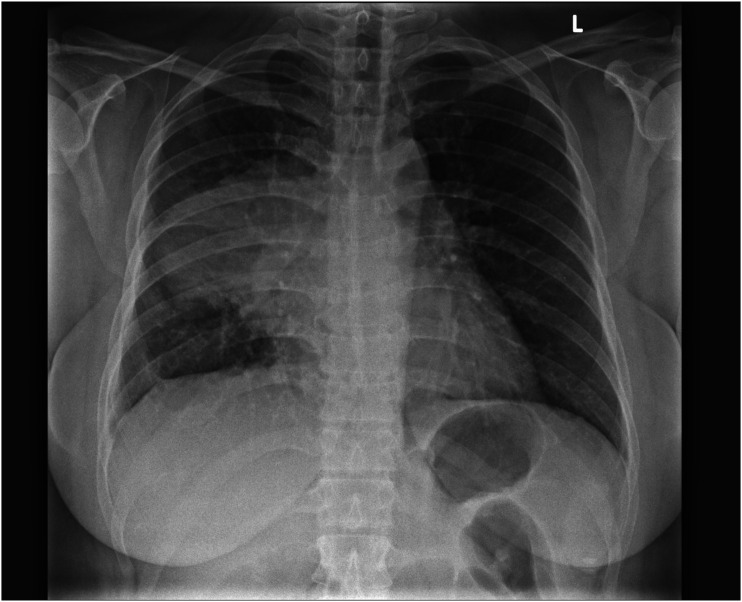

Teratomas are a common type of germ cell tumours which may be benign or malignant. Benign mature teratomas are the most frequent subtype and typically show intralesional fat and calcifications within a cystic mass. Immature/malignant teratomas are usually larger with irregular solid components, coarse calcifications, small amounts of fat, and with or without necrosis or haemorrhage. Teratomas can manifest in various anatomical locations, particularly in the sacrococcygeal, gonadal, mediastinal, retroperitoneal, and intracranial regions. This article explores the imaging characteristics and diverse locations of teratomas as well as discusses about possible differential diagnoses to facilitate early detection and ensure prompt treatment.

Abstract Image